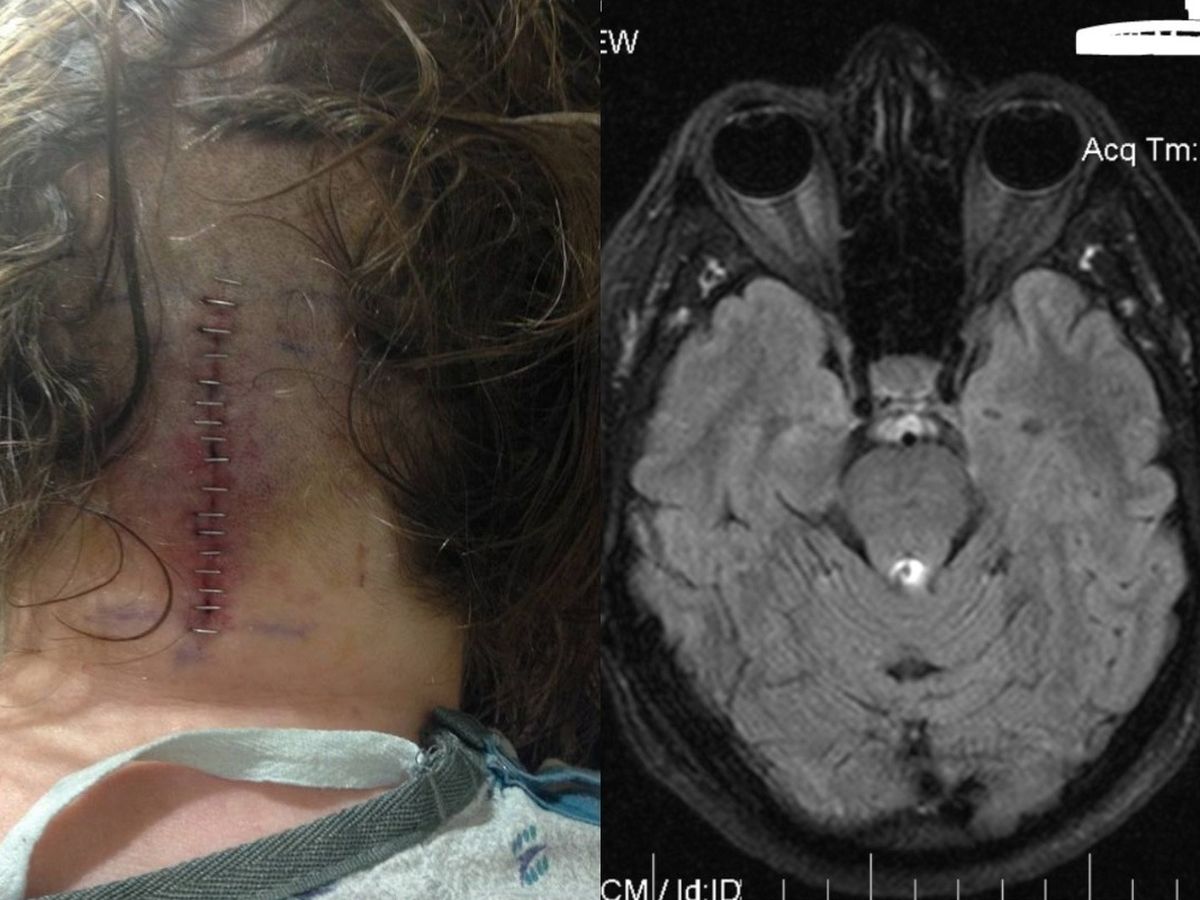

I was diagnosed with inoperable brain cancer in 2017. The tumor disabled me and left me with stacks of unpaid medical bills. Now my most recent MRIs show the tumor is growing again and doctors are recommending more chemotherapy. Which will mean lots more lab visits and MRIs.